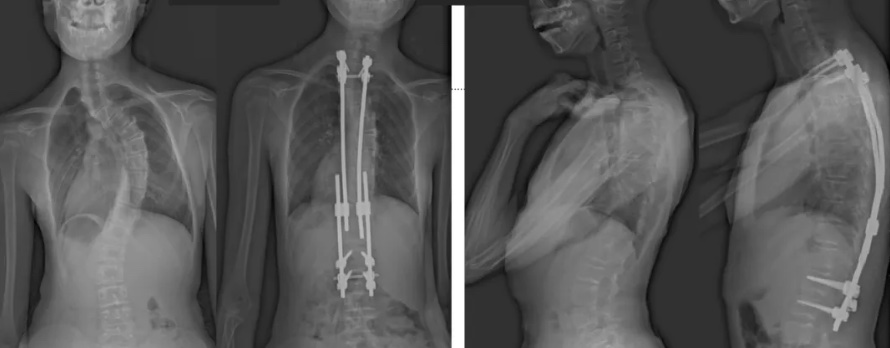

白瑪?shù)恼恍g(shù)前、術(shù)后對比圖(左側(cè));側(cè)位術(shù)前、術(shù)后對比圖(右側(cè))

術(shù)后第二天,白瑪就下地活動了。媽媽驚喜地發(fā)現(xiàn),白瑪一下子“長高”了近十厘米,重新抬起了頭,挺直了脊梁,肩膀也不歪了,可謂“脫胎換骨”。媽媽激動地錄制了一段白瑪走路的身影,把喜悅分享給全家。白瑪?shù)男g(shù)后檢查也提示,手術(shù)成功,恢復良好。

白瑪今年10歲,正在讀小學。媽媽發(fā)現(xiàn),白瑪經(jīng)常歪著肩膀,在反復提醒“站直了,別歪著”后,情況也沒有改善。近半年來,白瑪?shù)挠覀?cè)肩胛骨逐漸向后凸出。到醫(yī)院檢查后發(fā)現(xiàn),白瑪?shù)男刈荡嬖诿黠@的側(cè)凸畸形,是早發(fā)型特發(fā)性脊柱側(cè)凸。由于側(cè)凸較為嚴重,已經(jīng)失去了支具治療的機會。小白瑪才10歲,隨著身體的不斷成長,她的脊柱會越來越彎,肩膀會越來傾斜。這不僅影響體態(tài)和外觀,也可能限制心、肺等內(nèi)臟器官的發(fā)育,導致心肺功能下降、肢體活動不便,出現(xiàn)癱瘓,甚至死亡。對于白瑪這種情況,只能利用手術(shù)治療來矯正脊柱、阻止骨骼畸形進展。

經(jīng)過術(shù)前的精心準備和反復推演完善每個細節(jié),蔡思逸團隊順利為白瑪施行了“生長棒”矯形手術(shù)。這例耗時僅1.5小時的手術(shù)也是西藏本地完成的第一例使用“生長棒”技術(shù)來治療脊柱側(cè)凸的手術(shù)。